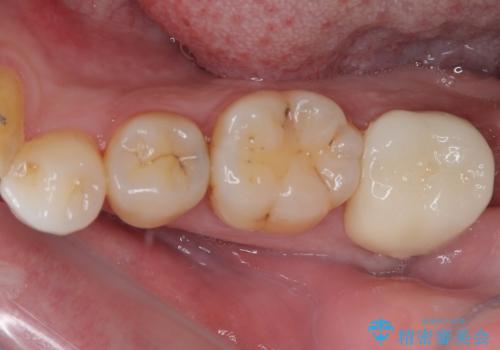

- 銀歯やむし歯でものが挟まるところが気になるとのことで来院された患者様です。

左上の奥歯は神経が失活しており、根管治療が必要な状態でした。

その他は銀歯のインレー(部分的な詰め物)が装着されており、それらはむし歯を除去した後にセラミックインレーにて修復治療を行い、左下と根管治療を行う左上の奥歯はオールセラミッククラウンにて補綴治療を行うこととしました。

目立っていた銀歯がなくなり、患者様には大変満足していただけました。